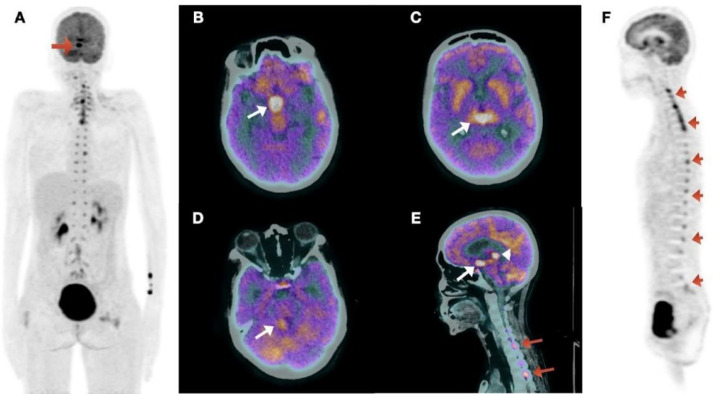

Pineal gland tumors are significant despite being rare (<1%) among all brain tumors. Germ cell tumors are the most common among the pineal gland tumors. Often affecting young adults, pineal gland germ cell tumors are hard to diagnose due to different symptoms and potential spread. But they rarely show leptomeningeal spread and extracranial metastases. Other differentials include primary tumors of the pineal region, Pineal gliomas, and metastases. The leptomeningeal spread of these tumors has not been studied so far. Conventional radiological imaging modalities are routinely used to diagnose and evaluate these tumors. We report a case here showing a pineal gland tumor with leptomeningeal spread detected by 18F-FDG PET/CT. Our case shows how pineal gland tumors can behave unusually and how 18F-FDG PET/CT can be crucial for accurately assessing the extent of the disease in the body to provide effective treatment. This case report illustrates the rare type of spread of pineal gland tumor and how 18F-FDG PET/CT helps detect this rare type of metastasis, thereby helping in prognostication and deciding further treatment of the patient.